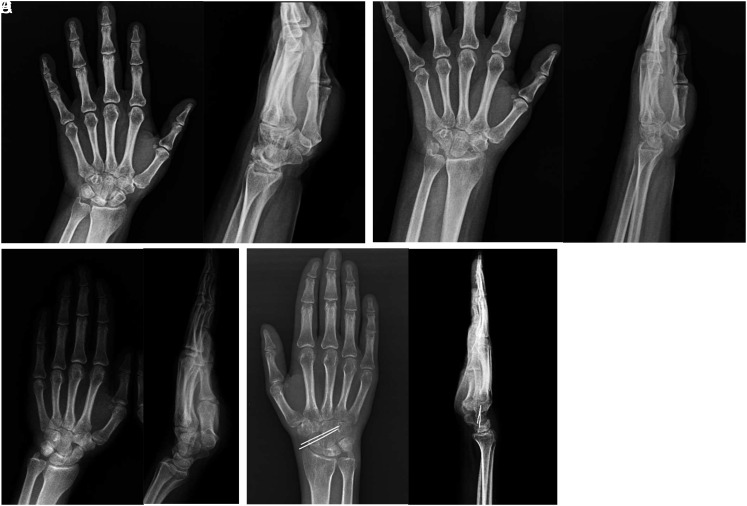

Abstract Image